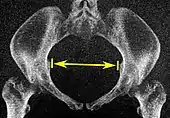

| Interspinous distance | ![]() |

The line between the closest bone points of the ischial spines | 9.5 to 11.5 cm.[6] | |